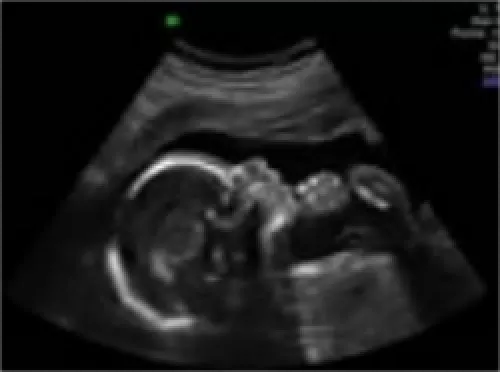

L’échographie du 2ème trimestre

voir le développement du fœtus (mesures du diamètre de la tête, de la circonférence abdominale, de la longueur du fémur ...), mouvements du bébé.

dépister des malformations , selon les recommandations de bonnes pratiques actuelles